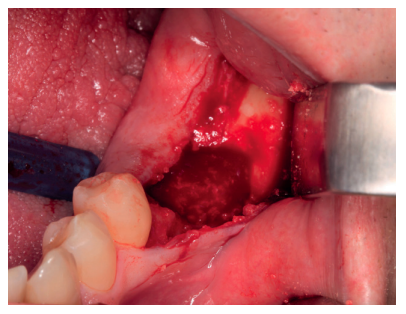

En una primera fase, se llevó a cabo la extracción del 3.7 y se empleó el mismo diente para realizar una preservación del defecto. Se realizó una anestesia troncular del nervio dentario inferior, nervio lingual y nervio bucal del lado izquierdo con articaína al 4% y adrenalina 1: 100,000 (Ultracaine®, Normon SL, Madrid, Spain). Se procedió a realizar una incisión supracrestal sin descargas y un despegamiento mucoperióstico a espesor total, asegurando la protección del colgajo lingual (Figura 3). Se realizó odontosección coronal para facilitar su extracción y, una vez removidas las raíces, se regularizaron los bordes y se dejó preparado para recibir el injerto (Figura 4).